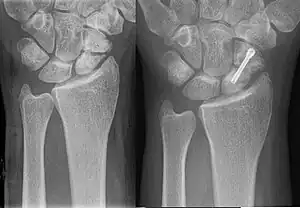

| An X-ray showing a fracture through the waist of the scaphoid | |

Scaphoid fractures are often diagnosed using plain radiographs and multiple views are obtained as standard.[9] However, not all fractures are apparent initially.[7] In 1/4 of cases, the clinical examination suggests a fracture, but the X-ray does not show it, even though there is indeed a fracture.[10] Therefore, people with tenderness over the scaphoid (those who exhibit pain to pressure in the anatomic snuff box ) are often splinted in a thumb spica for 7–10 days at which point a second set of X-rays is taken.[7] If a minimally displaced fracture was present initially, healing will now be apparent. Even then a fracture may not be apparent. A CT Scan can then be used to evaluate the scaphoid with greater resolution. The use of MRI, if available, is preferred over CT and can give one an immediate diagnosis.[11] Bone scintigraphy is also an effective method for diagnosis fracture which do not appear on Xray.[12]

A subtle scaphoid fracture

A more obvious scaphoid fracture on a scaphoid view X ray

Radiolucency around a 12 days old scaphoid fracture that was initially barely visible.[13]